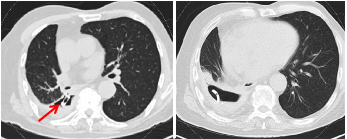

2014年2月,一名83岁男性,患有单发肺结节,后来被确诊为pT1bN0M0肺鳞状细胞癌,接受了微创右下叶切除术(图1)。患者在接受肺切除术三年后,因严重咳嗽并发烧而入院。尽管患者的发烧通过使用抗生素和胸腔闭式引流得到缓解,但咳嗽仍在继续,并且观察到导管大量漏气。胸部计算机断层扫描(CT)显示一9cm×7cm×6cm的脓胸腔、胸腔积液以及右下胸腔的引流管。支气管镜检查证实右下支气管残端与胸膜腔之间有直径约7毫米的瘘管。

图1. 术前胸部CT扫描显示一个9 cm×7 cm×6 cm的脓胸腔,内有胸腔积液,右下胸有导管和支气管支架(箭头)

根据其临床症状和影像学表现,患者在肺叶切除术后被诊断为右下段BPF伴脓胸,随后于2017年5月接受了内镜下放置覆膜支气管支架。此后,患者咳嗽减少,空气泄漏减少。然而,1周后,导管漏气和脓液排出再次增加,胸部CT进一步检查显示支架已移到脓胸腔(图1)。2020年4月7日,患者接受了肋骨切除胸廓造口术;切除了第7和第8肋骨的后部。胸腔内的支架和脓性胸腔积液排空并清创。然后,将2根引流管插入空腔,闭合伤口,用抗生素溶液冲洗空腔。对排出脓液进行培养,确定病原体为肺炎克雷伯菌和铜绿假单胞菌。7天后,患者开始出现明显的呼吸困难,出现皮下气肿;随后,闭式引流转为胸腔造口术(图1),在随后的几个月内定期更换敷料并应用加压绷带。一般情况好转后,患者再次接受了内窥镜治疗,在残端近端和远端之间放置Amplatzer房间隔缺损封堵器。引流后大面积漏气明显减少,病情逐渐稳定。